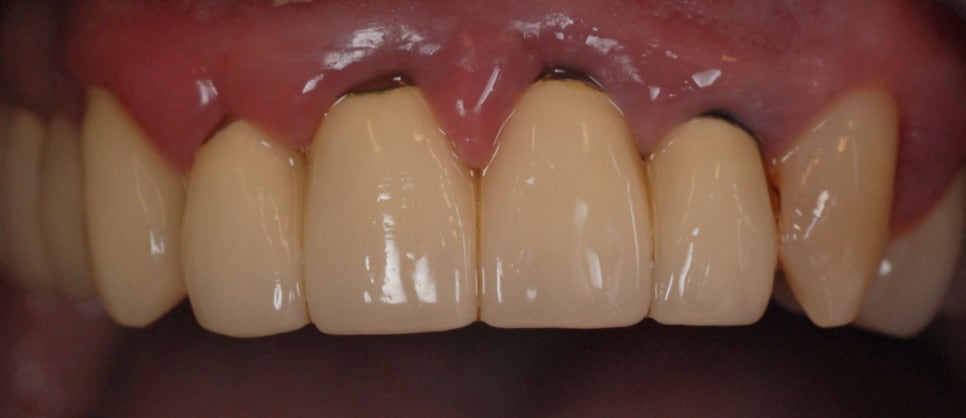

위 사진을 보세요. 크라운과 잇몸이 만나는 부분에 잇몸이 많이 부었죠? 왜 이런 현상이 발생하는걸까요. 경계는 치과에서 아주 중요한 부분입니다. 경계가 얼마나 잘 만들어졌냐에 따라 환자의 예후에 큰 영향을 줍니다. (출처: https://www.doccheck.com)